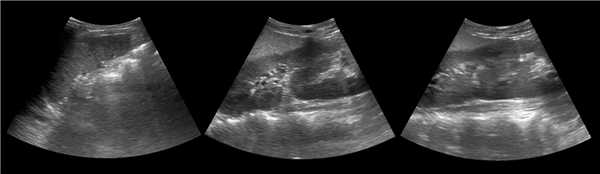

(Левый) Продольный ультразвуковой срез правой почки, визуализируется гипертрофирован ная бертиниева колонна, изоэхогенная корковому веществу почки.

(Правый) МРТ с контрастным усилением у этого же пациента (по поводу другого заболевания почки; не показано), визуализируется очаг такой же интенсивности сигнала, как и корковое вещество почки, сравнимое с гипертрофированной бертиниевой колонной.

5. УЗИ при бертиниевых колоннах почки:

• Исследование 8 режиме серой шкалы:

о Нормальный контур почки

о Обычно изоэхогенно по отношению к корковому веществу

о Цветовое и энергетическое допплеровское картирование позволяет визуализировать поток, идентичный корковому веществу

о Разделение центральных эхосигналов

(Слева) УЗИ, продольная плоскость сканирования: гипоэхогенное «объемное образование» в центре, которое выступает в почечную лоханку.

(Справа) КТ с контрастированием, аксиальная проекция: у этого же пациента установлено, что «объемное образование» — это нормальное корковое вещество почки, которое инвагинирует в почечную лоханку между чашечками верхнего полюса и меж полюсной областью почки. Обратите внимание на нормальный внешний контур почки. Бертиниевы колонны чаще всего выявляют с одной стороны и слева, как в данном случае: в 18% случаев они могут быть двусторонними.